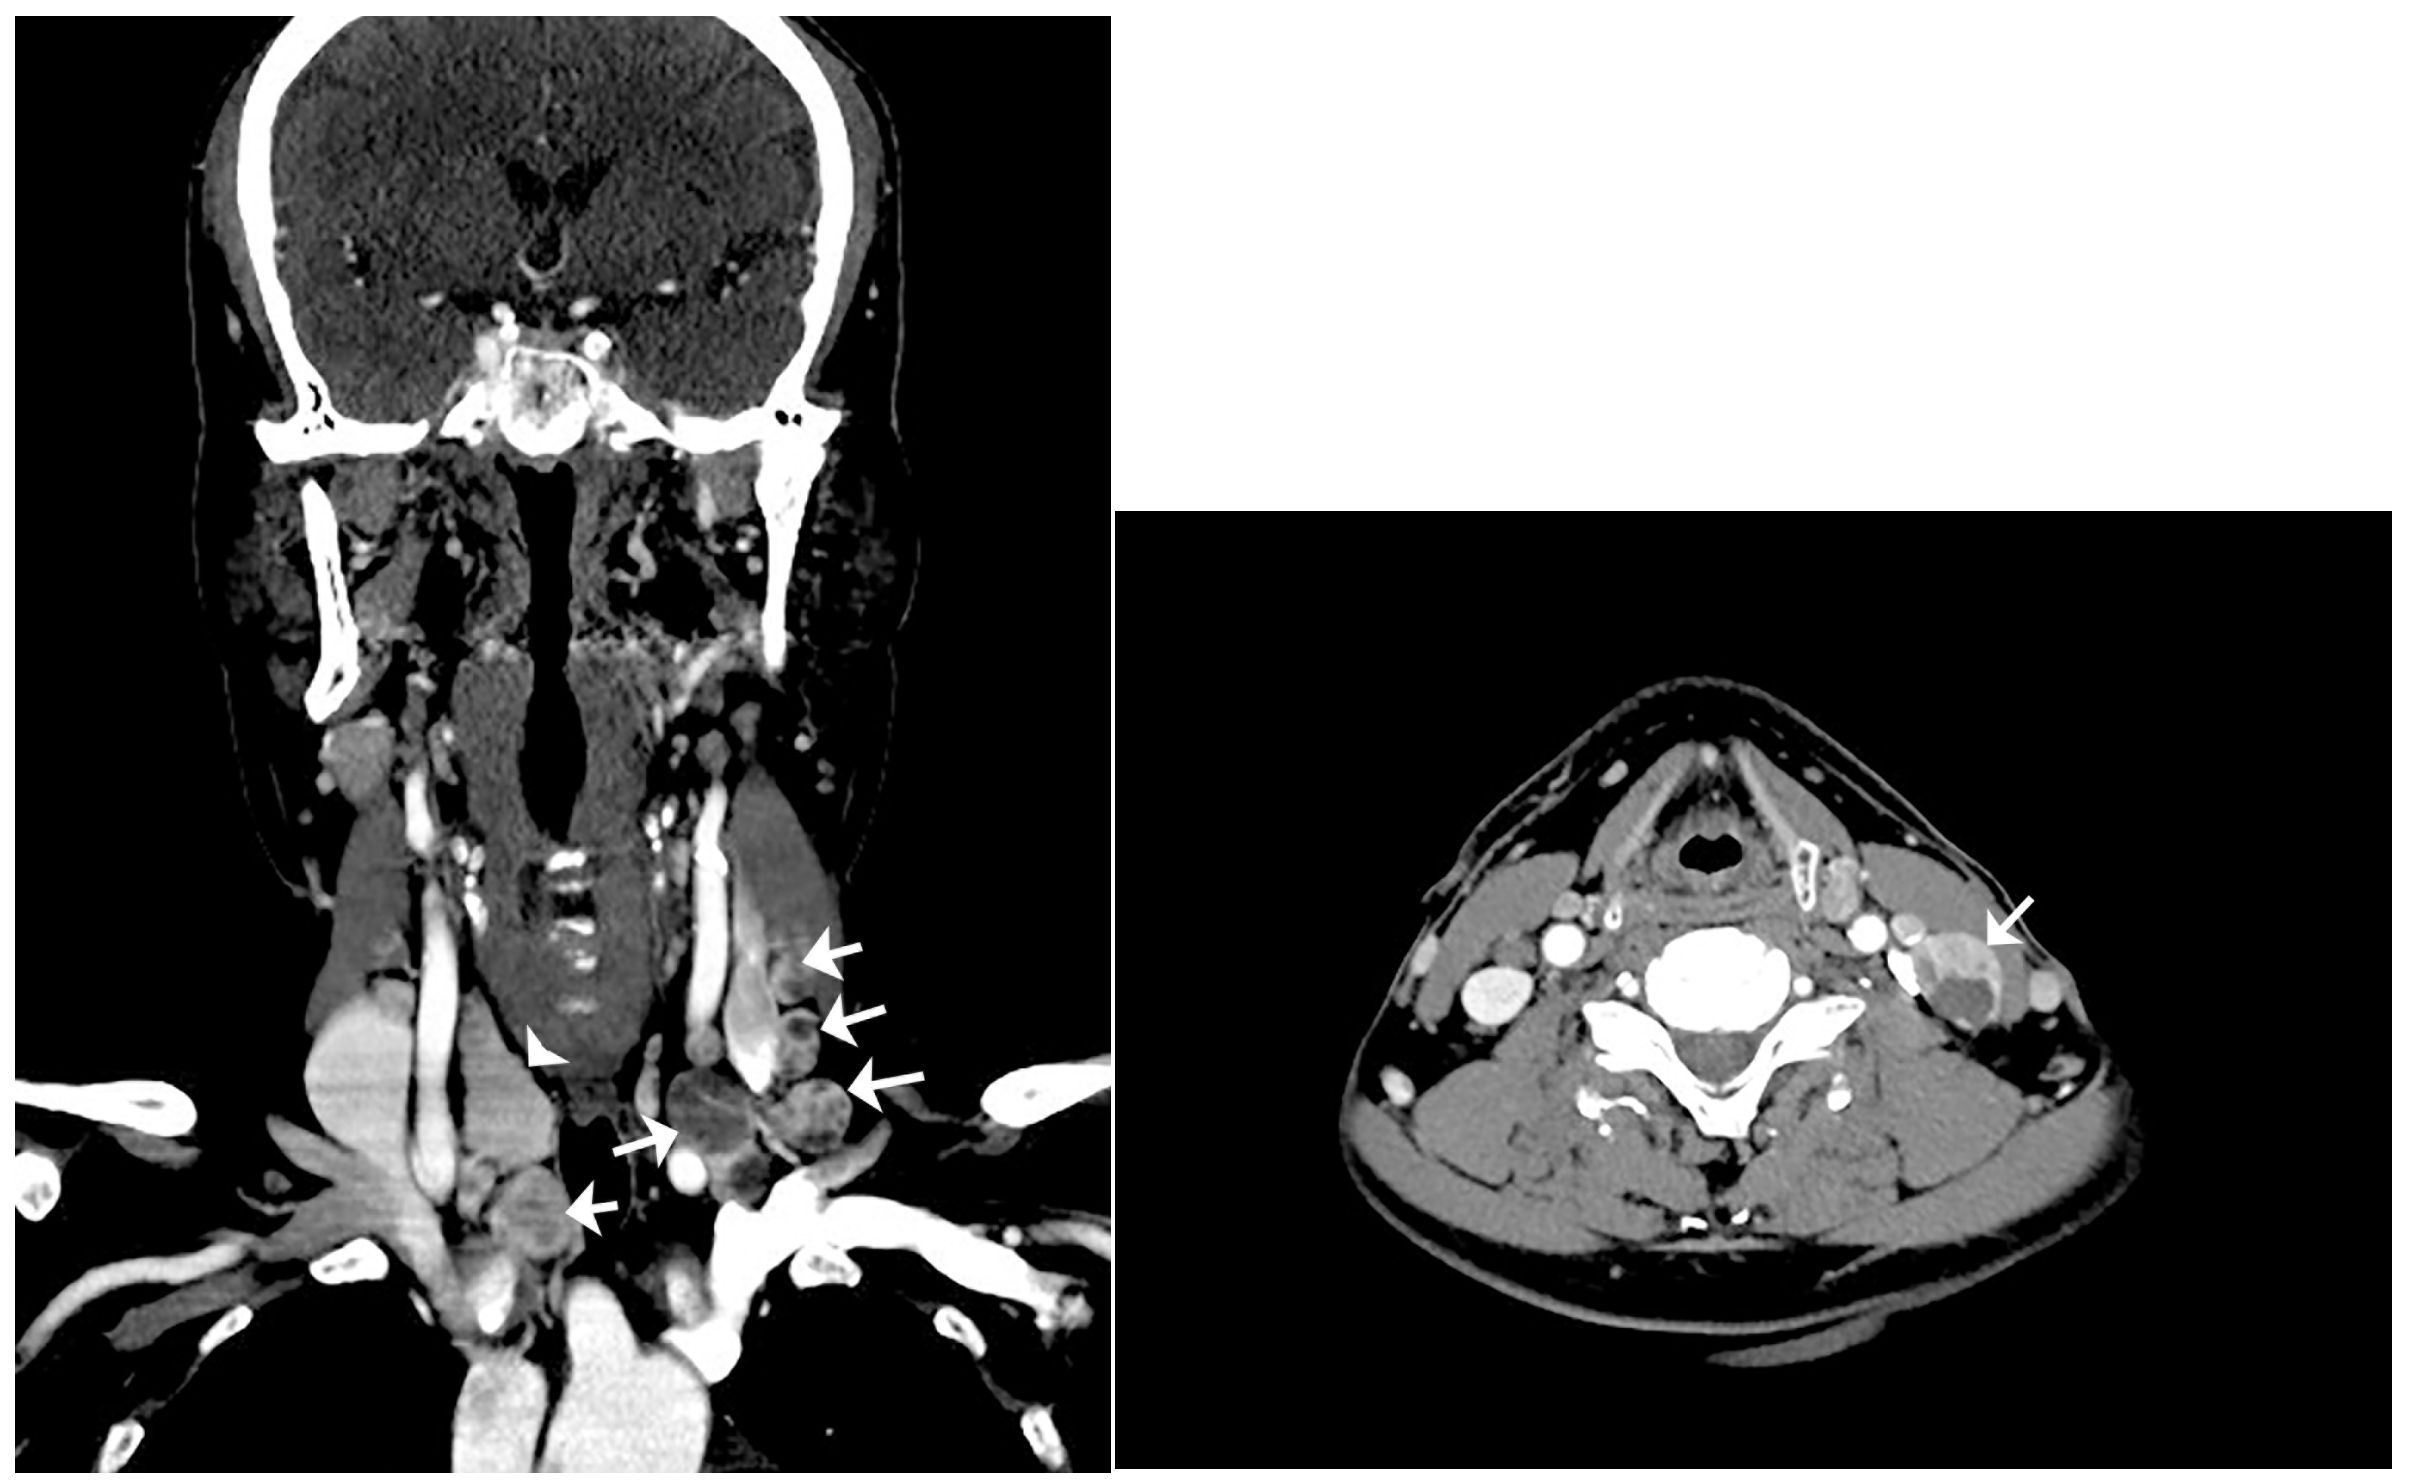

Computerized tomography (CT) scan of the neck. Left: coronal CT scan of the neck reveals multiple enlarged lymph nodes with internal variable cystic change involving bilateral neck of right level III and left levels II, III, and IV, and right lower cervical chain (arrow: multiple enlarged lymph nodes with cystic change; arrowhead: right lobe of thyroid). Right: axial CT scan of the neck reveals an enlarged lymph node with internal cystic change at left level III (arrow: the most enlarged lymph node with cystic change). Therefore, total thyroidectomy and cervical lymph node dissection were performed to distin-guish lymph node metastasis of occult thyroid cancer from seeding of thyroid tissue due to pre-vious thyroid surgery. Resected bilateral cervical lymph nodes were enlarged to the maximum dimensions of 3.5 × 1.7 × 1.0 cm. The cut surface of the lymph node and thyroid gland showed multiple variable-sized pale tan to brown solid nodules with cystic changes (Figure 3).